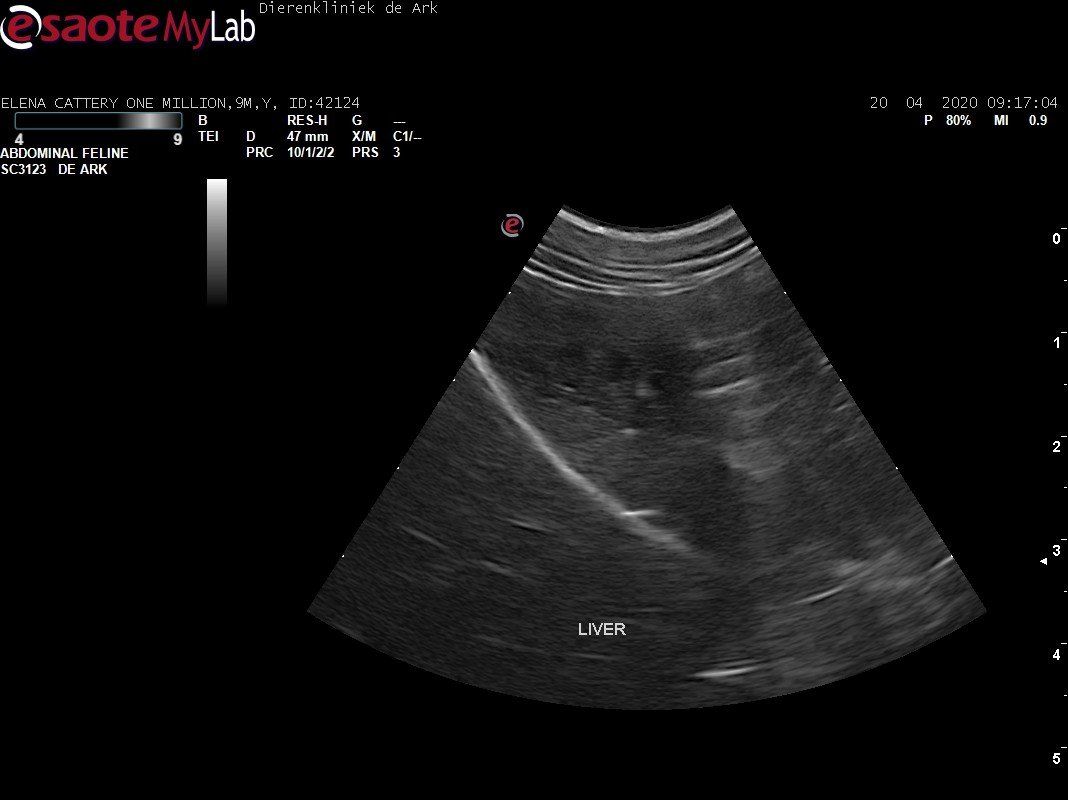

3,200 kg , echo en nieuw bloedonderzoek gedaan wat perfect ging door middel van gapabetine

Voor de garanties en om recht te hebben op medicatie bij herval eist Mutian diverse onderzoeken en controle momenten. Dit zijn bloedonderzoeken maar ook zoals hieronder te zien is echo's. Elana is volledig gecontroleerd op afwijkingen, gelukkig waren de echo's goed.